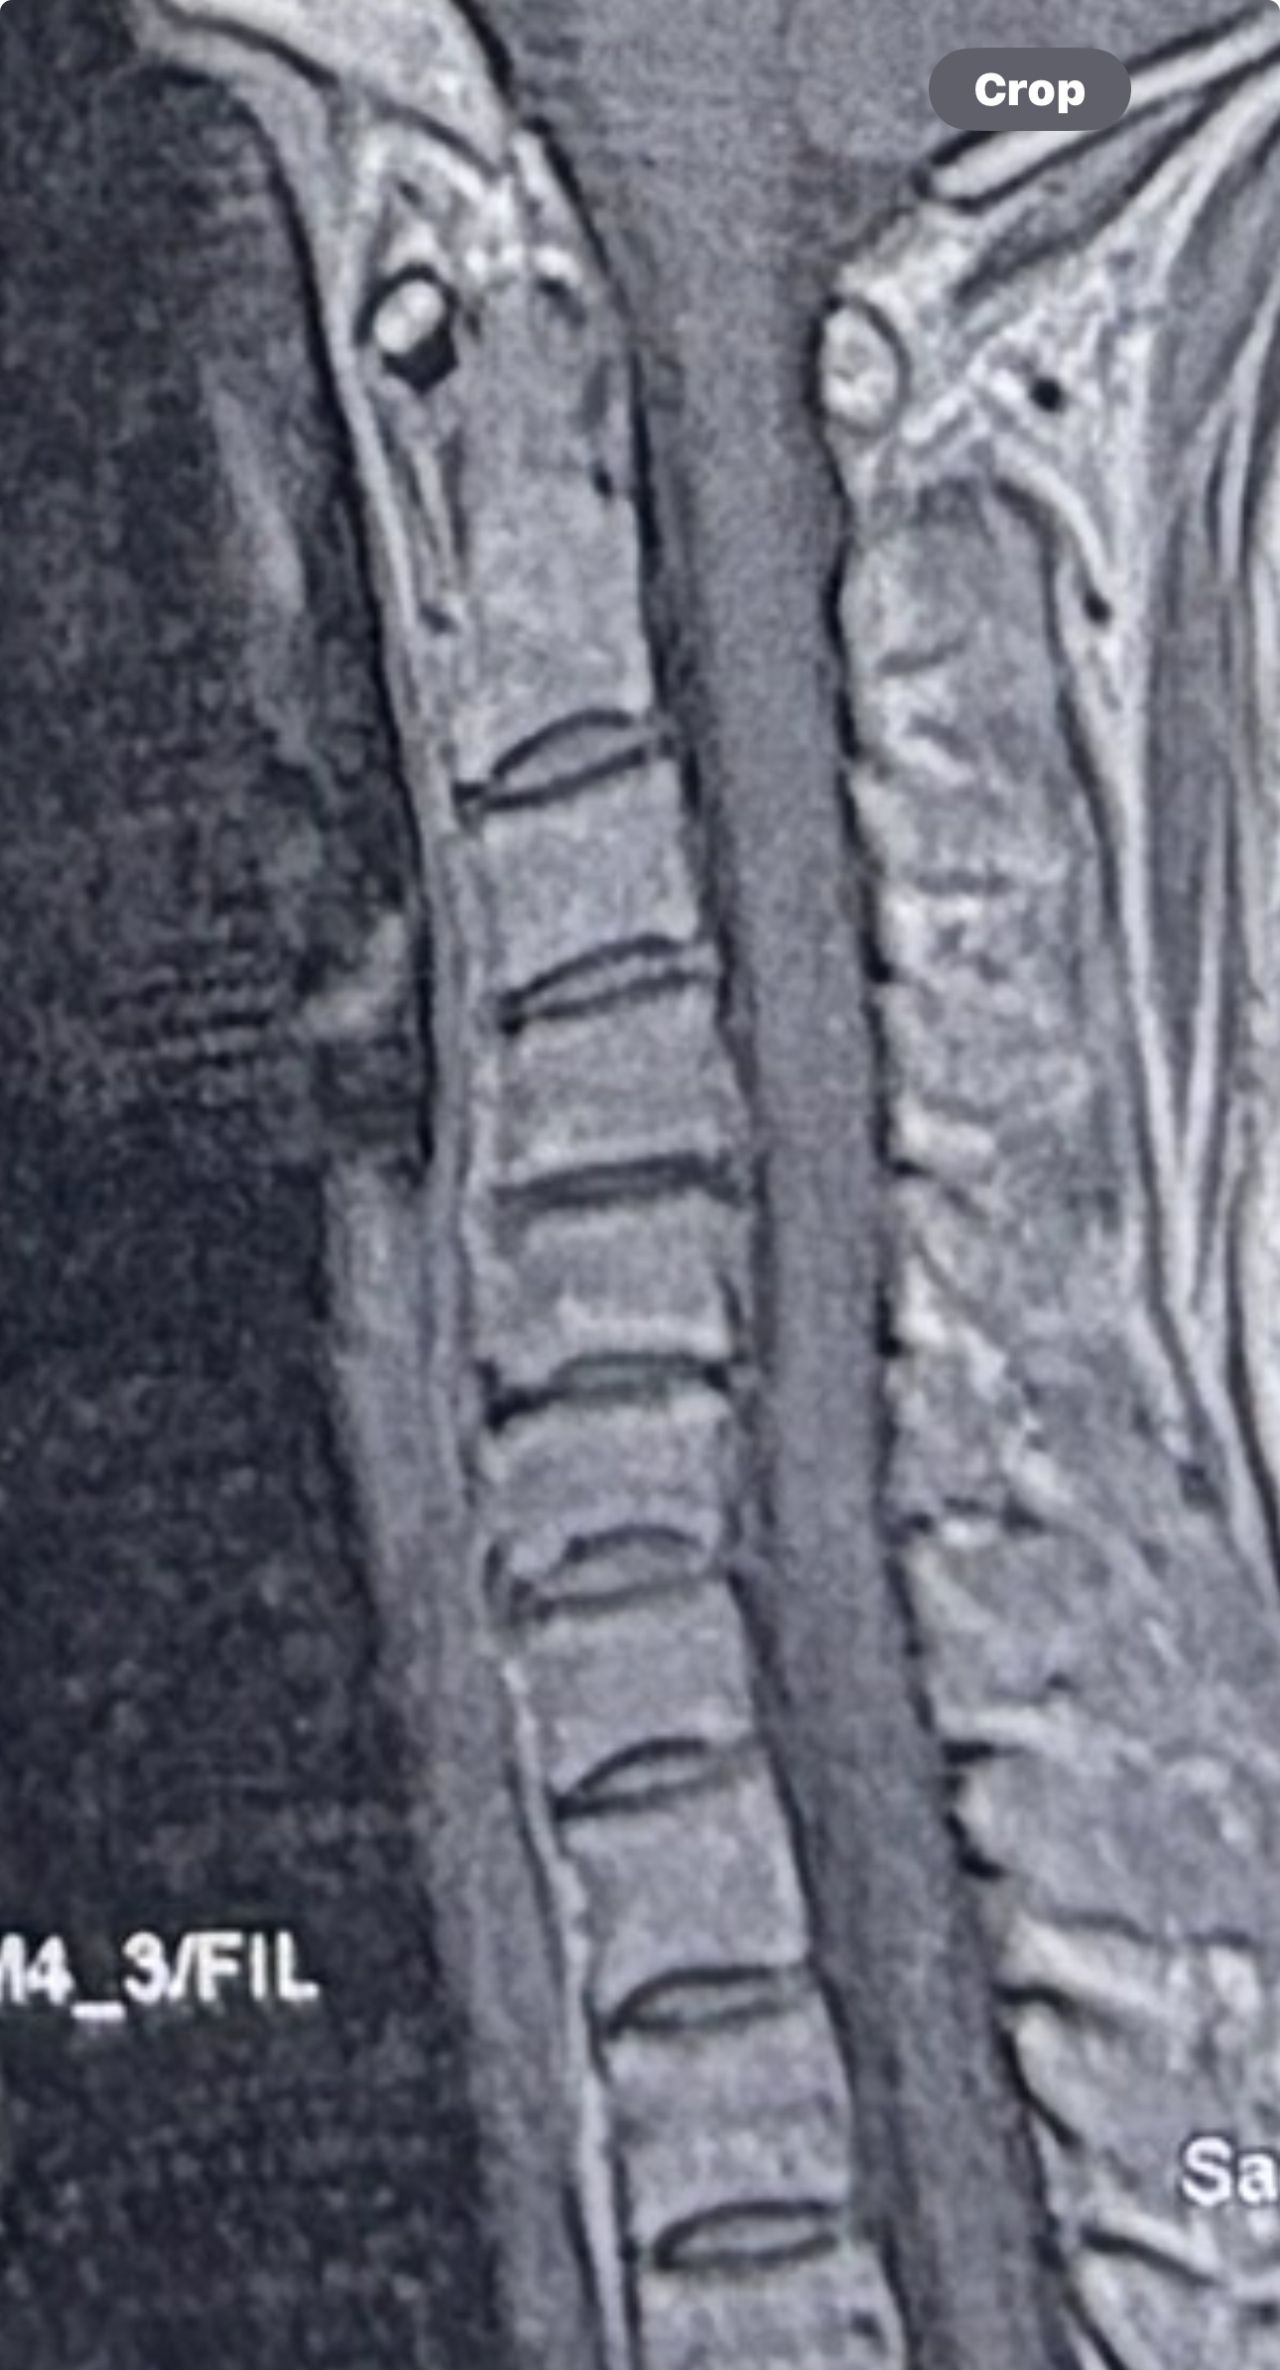

30 year old patient of mine with R. IVF disc extrusion of C 5-6 with R upper extremity pain and numbness without neurological deficit was suggested to have urgent surgery

got 20 sessions of chiropractic care in one month by me mainly using decompression and C0-C1 prone drop manipulation and 3 sessions of mild adjustment to segments above disc herniation. No direct adjustment to the involved disc extrusion

After treatment:

reduction of R. IVFdisc extrusion by more than 50%.

90% improvement in patient’s signs and symptoms and preventing of unnecessary expensive surgery

following one month of cervical chiropractic spinal treatments